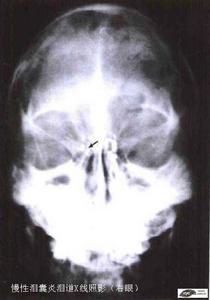

CT檢查

慢性淚囊炎形成囊腫時,表現為圓形或類圓形囊狀水樣密度影,膿腫的密度略高於水的密度。強化掃描有不同程度的環形強化。CT對於小的鈣化與結石也可顯示,表現為斑點狀的高密度影。另外可發現眶骨的增生、肥厚、破壞等改變。CT淚囊造影是將造影劑注入淚囊系統,同時進行CT掃描顯示其內結構,可發現鼻淚管阻塞、狹窄及擴張的部位及程度。並可顯示淚道系統及眶內軟組織、眶周結構、鼻部和鼻旁竇的病變。

慢性淚囊炎X線照影適應證:體積不大的慢性淚腺腫大或淚腺腫瘤。